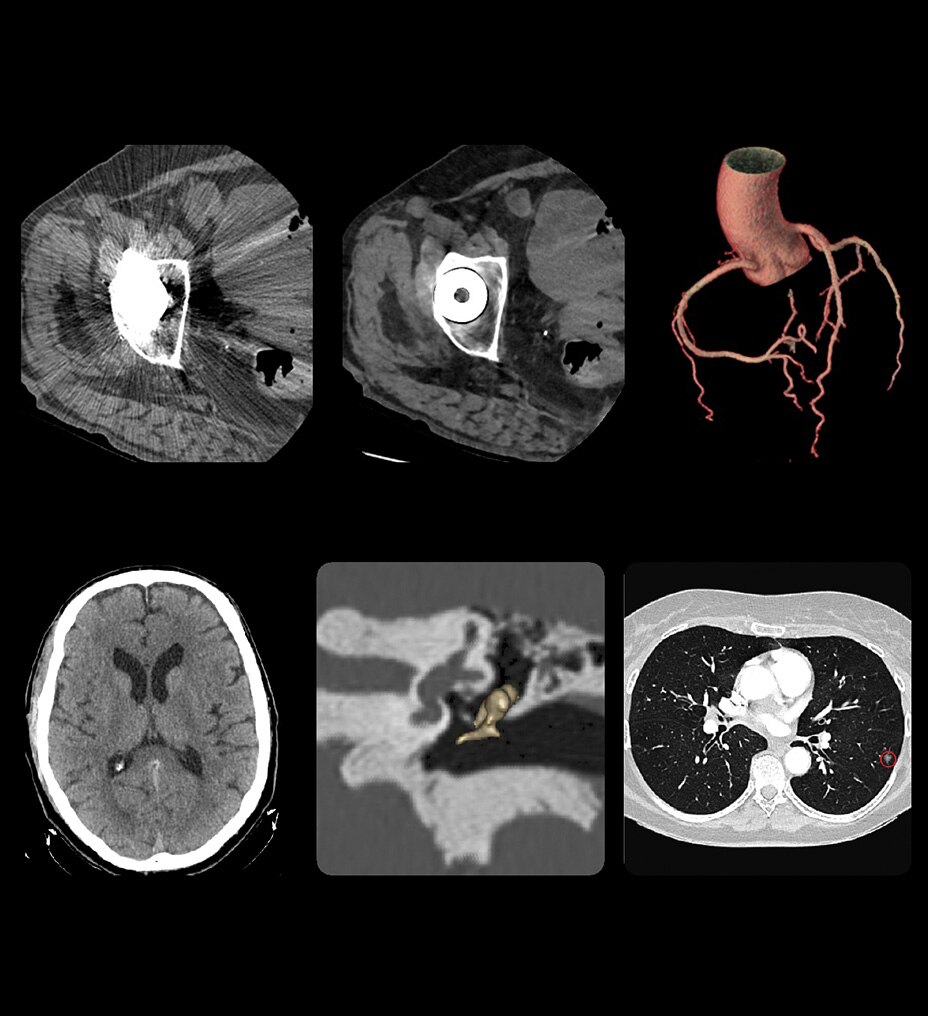

Birden fazla uygulamada çok yönlülük

Revolution Ascend; rutin, kardiyak, büyük bedenli hasta, Acil Servis ve girişimsel dahil olmak üzere çoğu ortama yönelik özelliklere sahiptir.